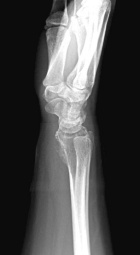

18 year old female with persistent and worsening wrist pain for four months